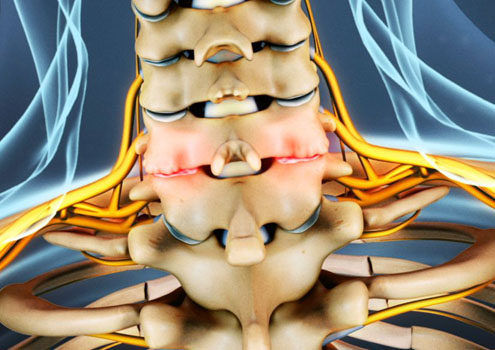

دردهای گردنی

Cervical Pain